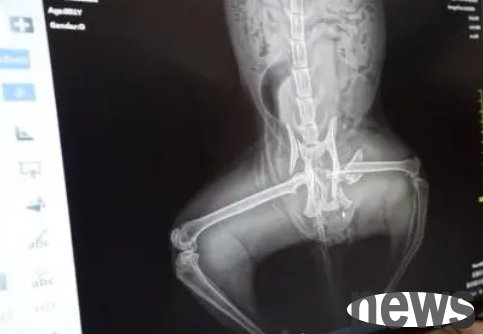

The results of the cat's radiograph

Seeing that the cat was very cooperative, he got into the flight box. The little brother then took the cat directly to the pet hospital. After arriving at the pet hospital, after some x-ray examinations by the pet doctor, the pet doctor counted the results of the cat's x-rays and told the little brother that this poor stray cat had a total of 4 fractures, the most serious of which was an open fracture in the cat's left leg. In addition, the cat also had pelvic fractures, ischium fractures, and femur fractures. Since we don’t know whether the cat can defecate on its own, after checking the cat’s injuries, helping the cat debridement, and bandaging the wound, the pet doctor suggested that he keep the stray cat in the pet hospital for observation for a few days. After confirming the cat’s condition, he can then arrange for follow-up treatment...